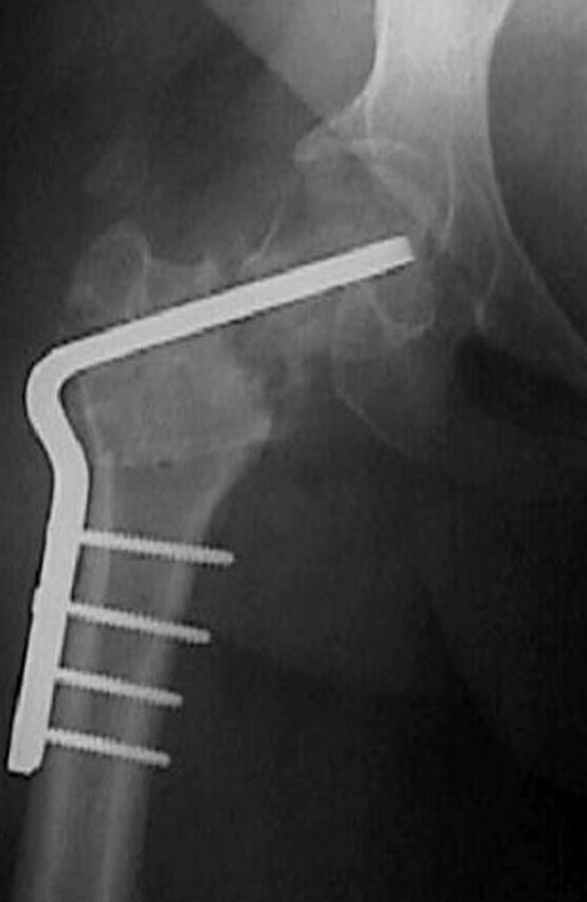

Если, например, доводится лечить больных с псевдартрозами шейки бедра, то надобность есть, и приходится. См. приложение.

На рисунке N1 предоперационный план лечения ложного сустава шейки бедра- линия ложного сустава, угол и направление введения импланта, клиновидная остеотомия в градусах и миллиметрах, второй снимок после коррекции, расчет, на сколько удлиняется конечность и размеры импланта;

N3 рисунок окончательный снимок, после операции моя рентгенограмма должен выглядеть примерно как эта картина. На N4 снимке клин перед удалением; N5 послеоперации 3 нед.; N6 окончательная рентгенограмма.

варус при проксимальном отделе 95 градусной пластиной.